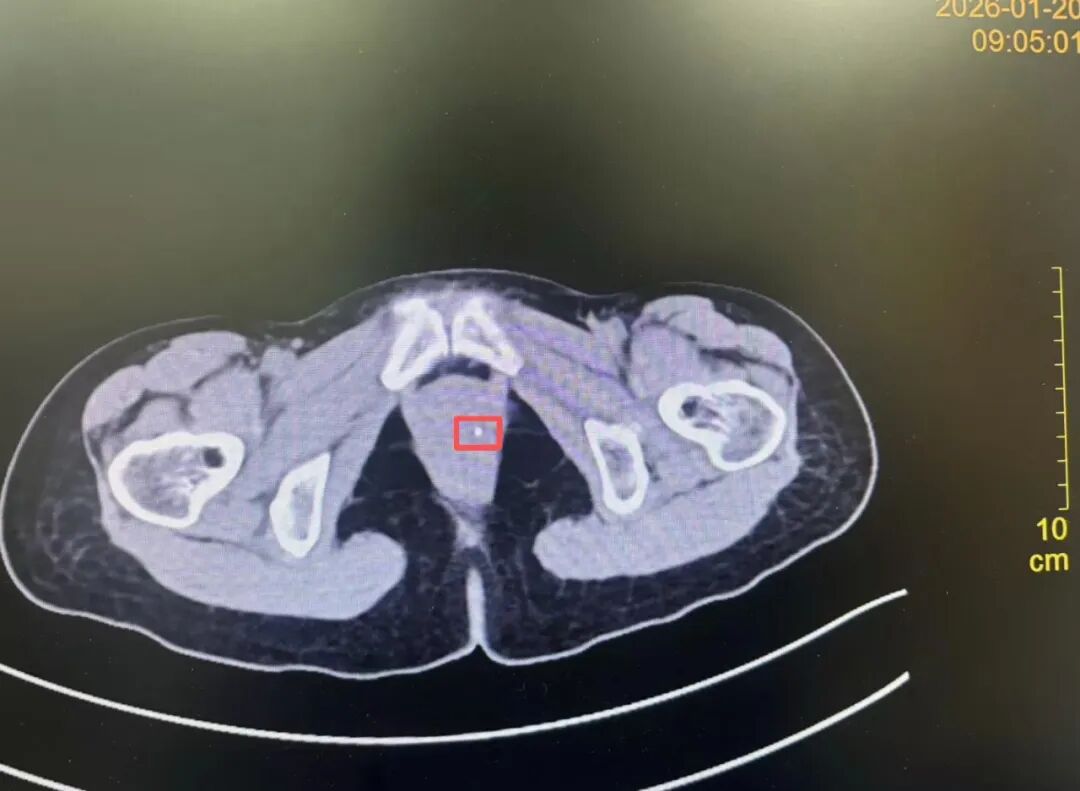

三年之「坠」终解除——异物取出

术后 CT 复查显示原异常影像区域明显改善

术后复查 CT 显示: 原手术区域的异常影像明显改善。